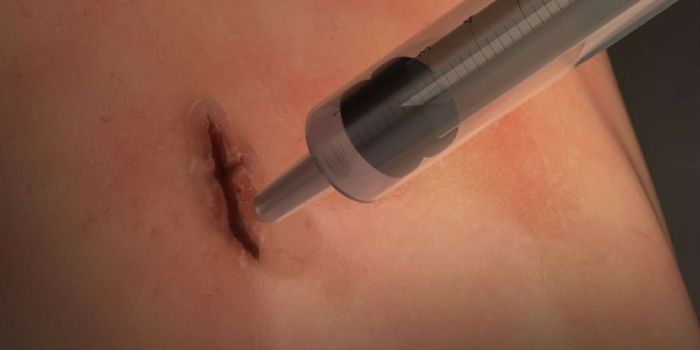

JUL 21, 2020Clinical & Molecular DXPicture this: a hiker on a backcountry trail falls down a rocky embankment, and is left with a deep gash on the leg afte ...

JUL 22, 2021Clinical & Molecular DXWounds are an ideal environment for microorganisms to thrive. Their presence can easily overwhelm immune defenses at the ...